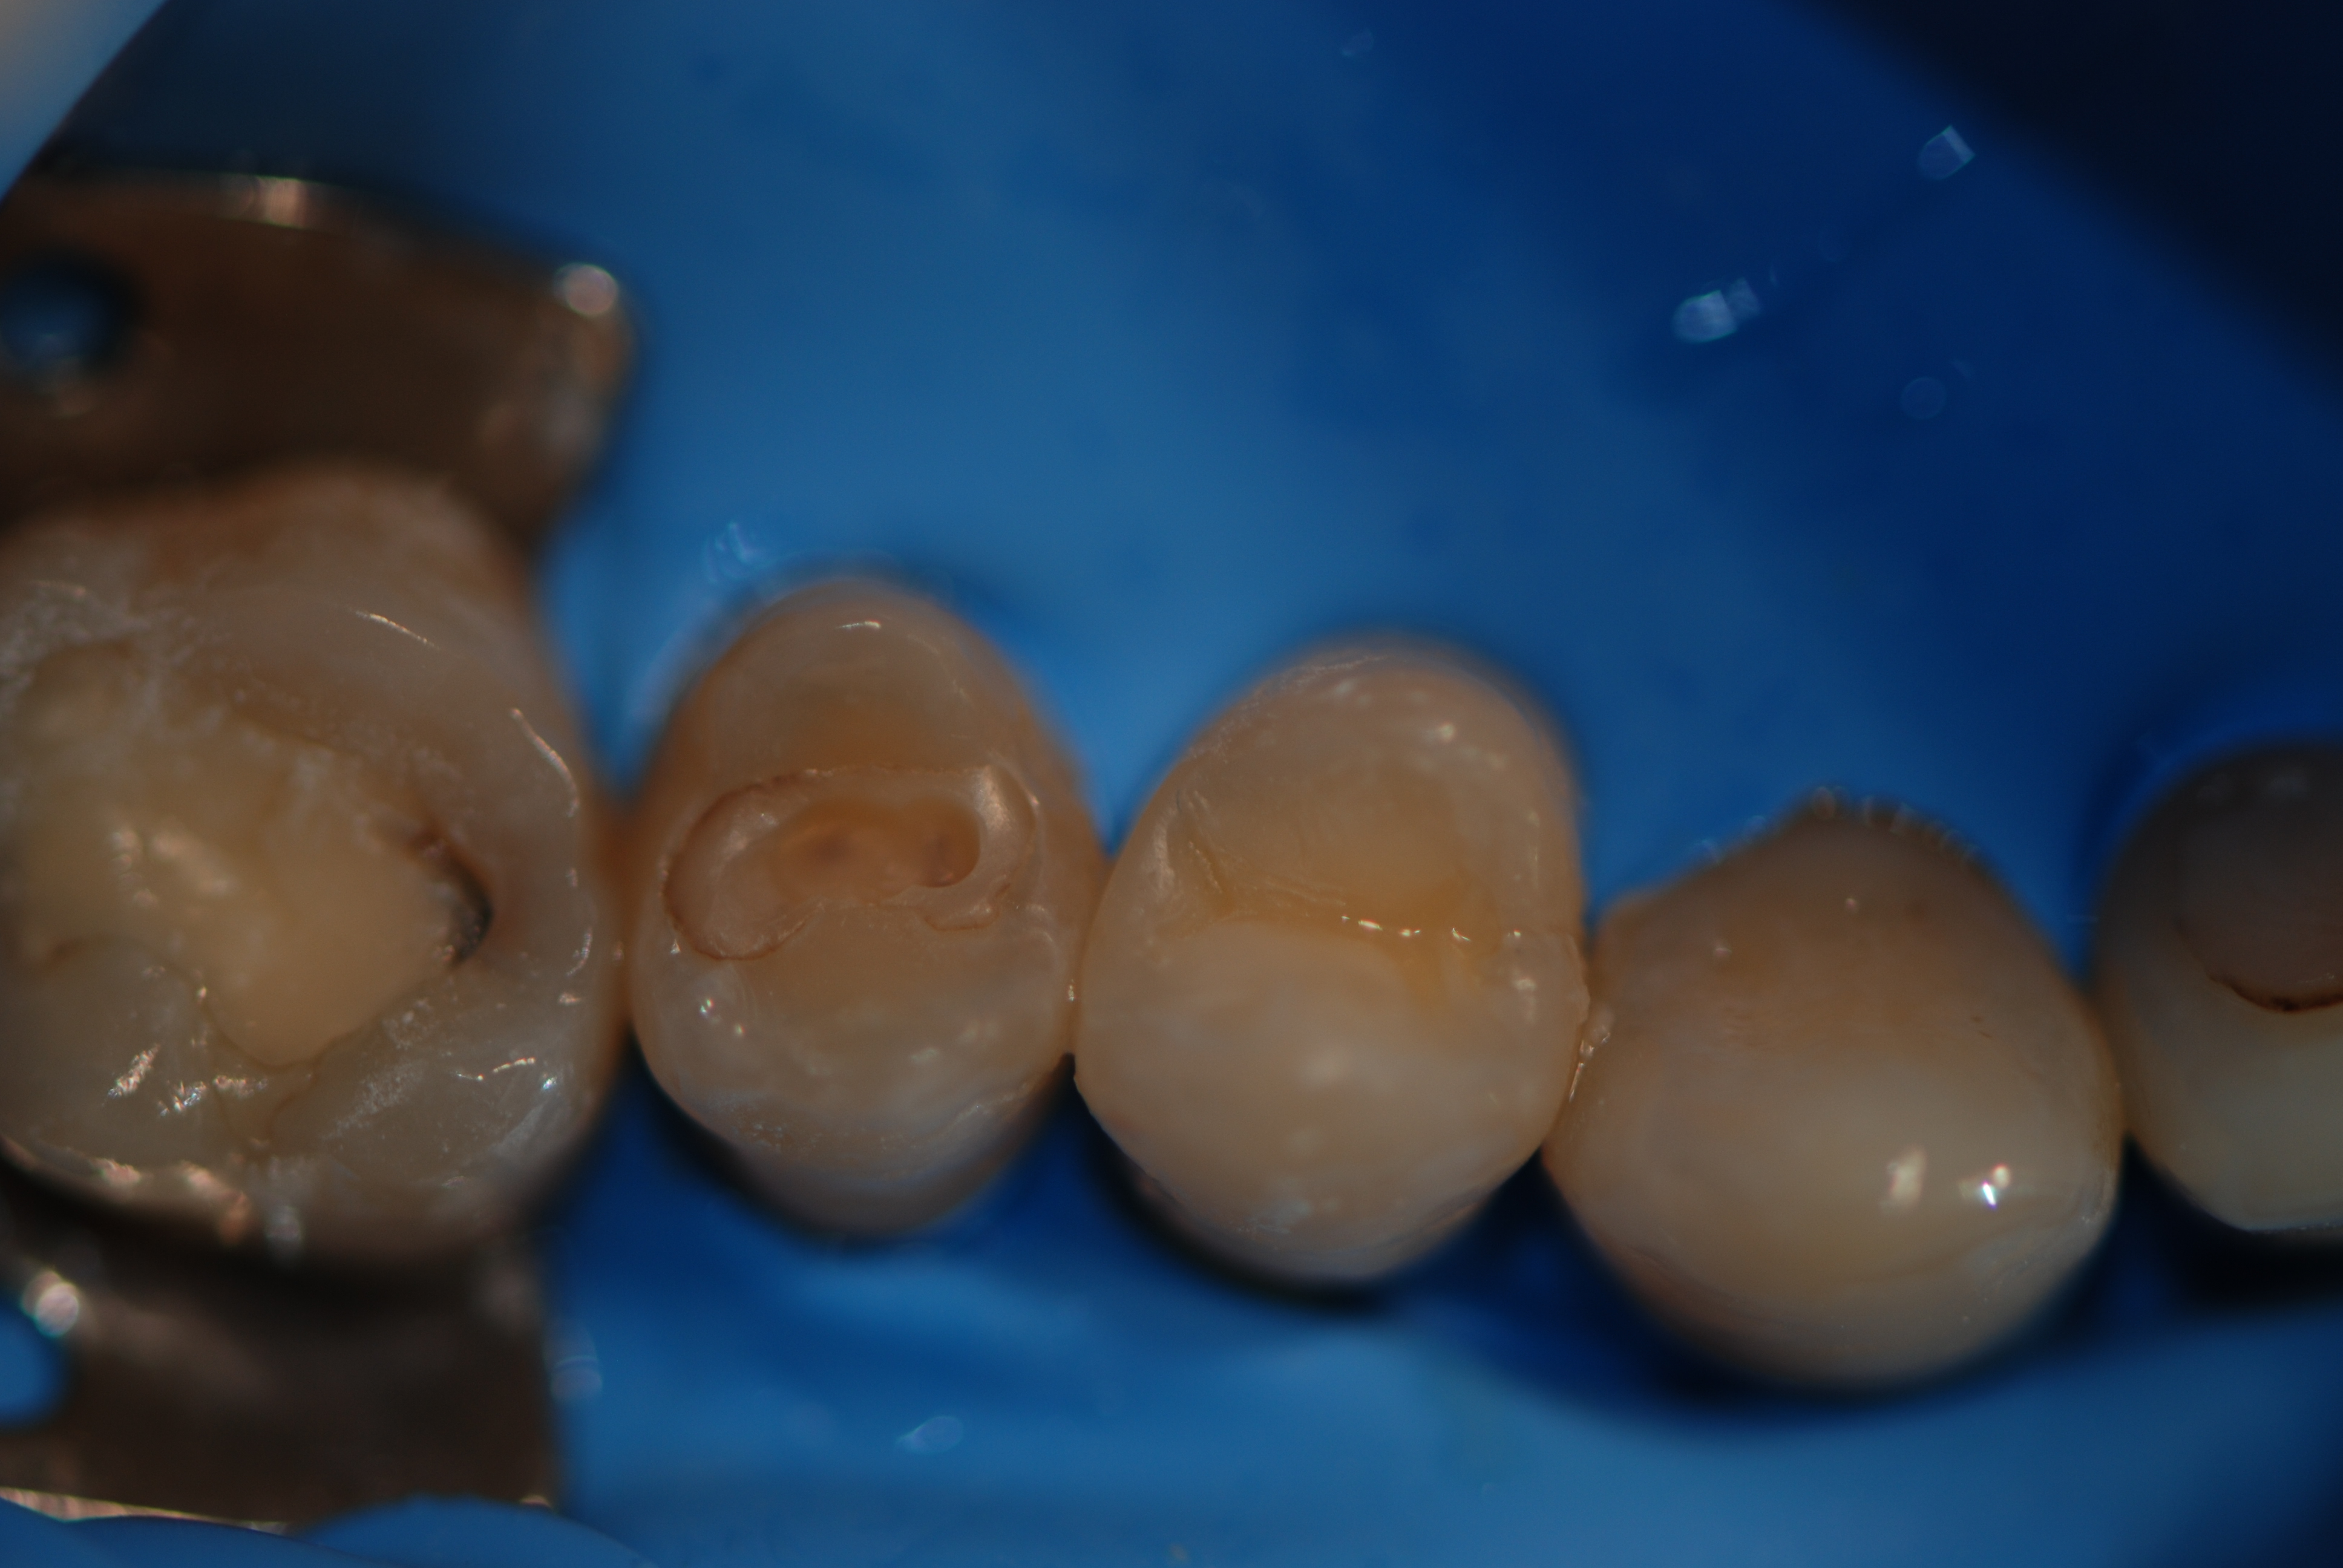

Ricostruzioni estetiche di due vecchie otturazioni infiltrate.

Situazione iniziale. 1.4 è stato già in precedenza ricostruito